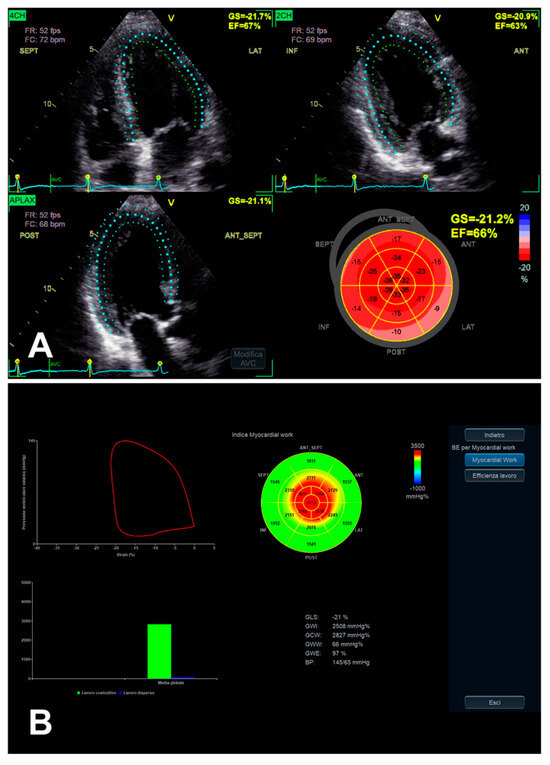

3.1. Left Ventricular Global Longitudinal Strain

3.3. Left Ventricular Myocardial Work